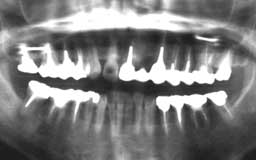

★ Oさん 61歳

Oさんもそんななかのひとりです。来院直後の6年間にブランクがあって、その時失った下

顎の前歯部を除けばかなりの状態をキープしているといえます。61歳としては余りにも条

件が良すぎたためにメインテナンスを積極的に勧めなかったことが少し悔やまれます。

| Oさん 初診時 61歳 男性 上顎臼歯部に中程度以上の歯槽骨破壊が認められるが残存する歯の数は多い |

Oさん 20年後 81歳歳 補綴(ほてつ)物が多いことに不満を感じるが親知らずを含む残存歯数27本は立派 |